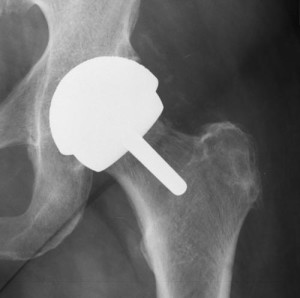

In July 2008, artificial joint maker Zimmer, Inc. temporarily suspended sales of its Durom Cup hip replacement system to investigate reports of problems and early failure rates from patients and orthopedic surgeons. The product had only been on the market for two years. In August 2008, after a month-long investigation, the company chose not to issue a Zimmer hip recall, but instead re-released the Durom Cup hip implant back onto the market accompanied with updated surgical instructions. Zimmer stated that the Durom Cup was not defective, and that any problems with device dislocation and loosening were the results of surgeon error.

The new metal-on-metal hip replacement system was advertised as being a superior option to older metal-on-plastic and metal-on-ceramic devices, with longer durability and improved strength and flexibility. A single piece of material made of cobalt chromium alloy, it was meant to be used in combination with Zimmer’s large diameter heads, which would fit inside the cup in the hip joint.

Dr. Dorr told Zimmer that several of these patients needed hip revision surgery—more than would be expected. X-rays were showing that the socket was separating from the hipbone, rather than fusing with it. The new hip was intended to last for up to 15 years, but instead, was causing pain within a few months to a couple years.